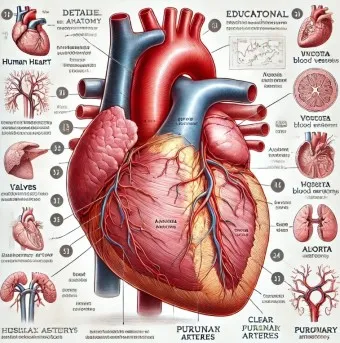

1. 심장 관련 원인

- 부정맥: 정상 심박수 범위 60-100회/분 이탈

- 심장 판막 이상: 증상 발현 시 심박수 변동 20% 이상

- 빈맥증: 휴식 시에도 심박수 100회/분 이상

- 서맥증: 심박수 60회/분 이하로 저하